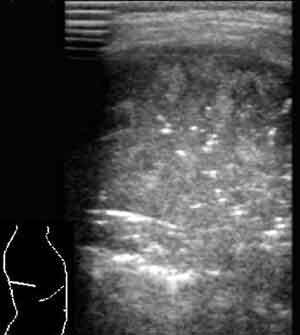

Эхография в диагностике заболеваний легких у детей.

Рис. 6. Формирующиеся участки деструкции в безвоздушном пневмоническом очаге.